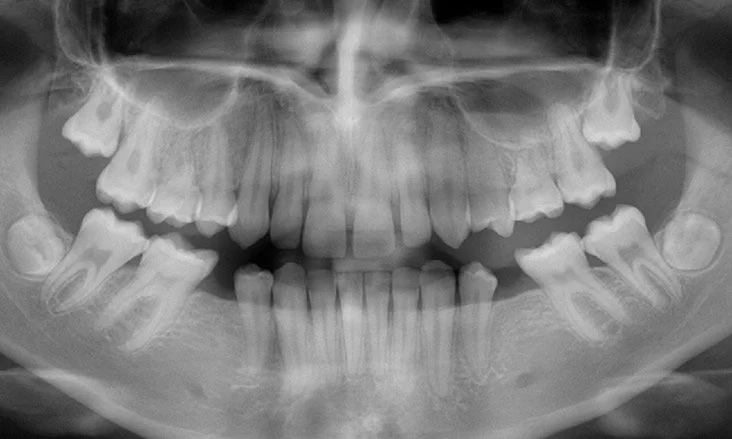

Paediatric dentistry

tips for dental practicioners

Clinical Tips created by Paediatric Dentists

Dealing with children and special needs patients can be very stressful and uncertain. Clinical tips and hints can help you to navigate this tricky area. You will find your own way of dealing with children, however sometimes seeing someone else in action can help you along.